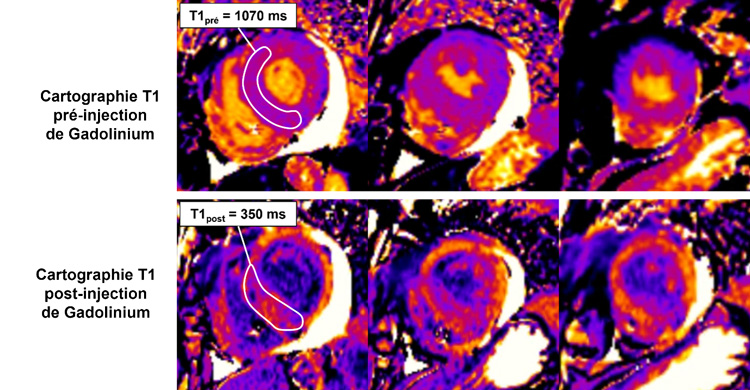

Figure 2 : Cartographie T1 pré et post injection de gadolinium

Coupes petit-axe basal, médian et apical

La mesure de l’hématocrite permet de calculer la formule du volume extracellulaire (ECV) mesuré à 41 %.

Figure 6 : Cartographie T1 pré et post injection de gadolinium - Coupes petit-axe basal, médian et apical

Valeur d’ECV mesurée à 41 %.

- La mesure du T1 mapping à 1 070 ms n’est pas très élevée pour l’âge du patient (norme < 1 100 ms pour cet âge).

- Par contre, la mesure du volume extracellulaire (ECV) est franchement élevée à 41 % (norme < 27 %).

- À noter que cette divergence entre T1 mapping normal et ECV élevé peut notamment être décrite chez les patients avec amylose cardiaque.